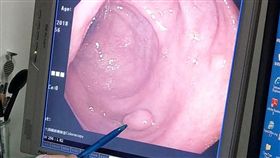

婦喝熱豆漿喉嚨卡罹癌!超多人都有這習慣

人的身體有許多警訊,大家可以透過觀察身體的異常變化,...

食道癌致死率高 原來是吃太多這個!

2018年12月藝人安迪和前裕隆集團總裁嚴凱泰,相繼...